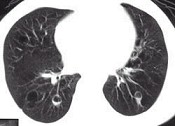

- 单项选择题女,23岁, 咳嗽咳痰反复发作,根据CT图像, 应考虑为 ( )

A、支气管扩张并感染

B、多发肺气囊肿

C、多发性肺囊肿并感染

D、多发性肺脓肿

E、大叶性肺炎